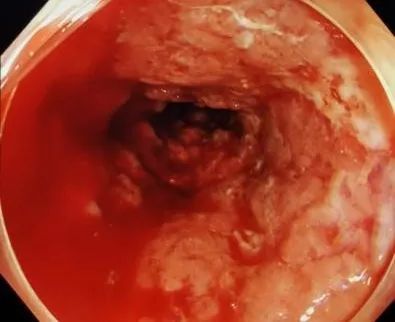

直肠炎(重度)距肛门15cm以下直肠粘膜水肿及大量斑片状充血,血管网

起直至直肠可见结肠袋变浅,黏膜呈广泛弥漫性充血水肿,表面大量溃疡及

粘膜充血水肿伴出血,结肠袋消失;图10 粘膜青紫,坏疽